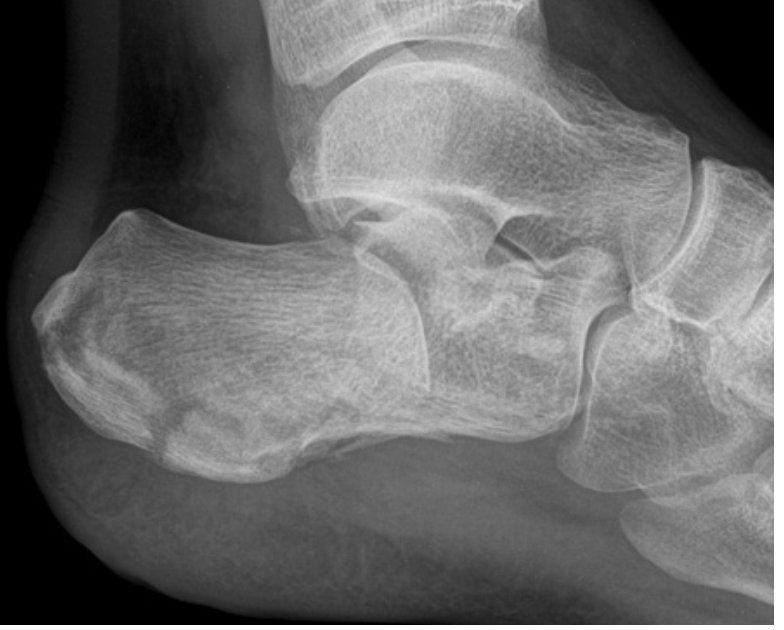

What’s going on in this x-ray? [1]

Calcaneal fracture - Lateral view